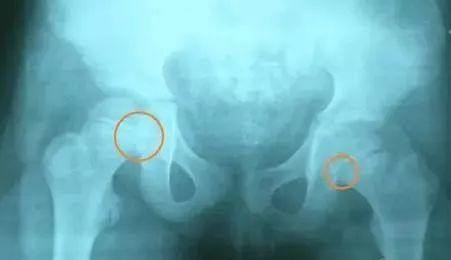

Kline线(克莱恩线)沿股骨颈上缘划线并沿股骨头方向的延长线。正常此线应切割部分股骨头骺部,若骨骺位于该线内方,提示股骨头骨骺向下滑脱。